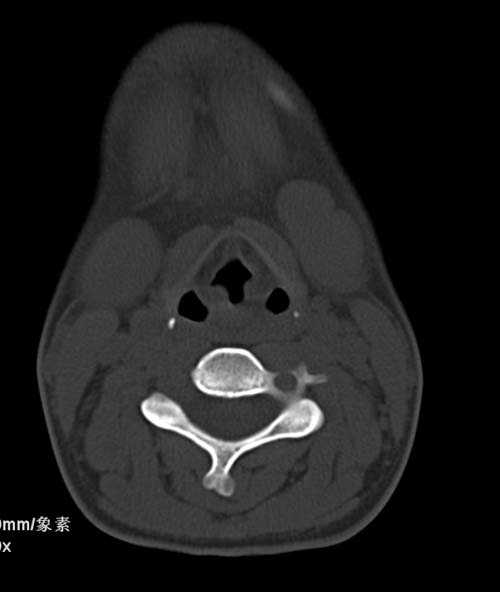

标题: CT22662:女 23 自述双侧颌下腺肿大年余 近来疼痛 左侧明显 [打印本页]

标题: CT22662:女 23 自述双侧颌下腺肿大年余 近来疼痛 左侧明显

见双侧颌下腺略肿大  未见结石及钙化 考虑双侧慢性炎症 ?请指教